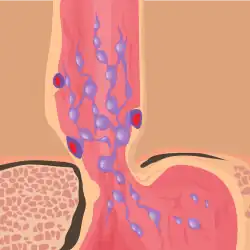

The upper two thirds of the esophagus are drained via the esophageal veins, which carry deoxygenated blood from the esophagus to the azygos vein, which in turn drains directly into the superior vena cava. These veins have no part in the development of esophageal varices. The lower one third of the esophagus is drained into the superficial veins lining the esophageal mucosa, which drain into the left gastric vein, which in turn drains directly into the portal vein. These superficial veins (normally only approximately 1 mm in diameter) become distended up to 1–2 cm in diameter in association with portal hypertension.

Normal portal pressure is approximately 9 mmHg compared to an inferior vena cava pressure of 2–6 mmHg. This creates a normal pressure gradient of 3–7 mmHg. If the portal pressure rises above 12 mmHg, this gradient rises to 7–10 mmHg.[5] A gradient greater than 5 mmHg is considered portal hypertension. At gradients greater than 10 mmHg, blood flowing through the hepatic portal system is redirected from the liver into areas with lower venous pressures. This means that collateral circulation develops in the lower esophagus, abdominal wall, stomach, and rectum. The small blood vessels in these areas become distended, becoming more thin-walled, and appear as varicosities.

In situations where portal pressures increase, such as with cirrhosis, there is dilation of veins in the anastomosis, leading to esophageal varices.[3] Splenic vein thrombosis is a rare condition that causes esophageal varices without a raised portal pressure. Splenectomy can cure the variceal bleeding due to splenic vein thrombosis.

Varices can also form in other areas of the body, including the stomach (gastric varices), duodenum (duodenal varices), and rectum (rectal varices). Treatment of these types of varices may differ. In some cases, schistosomiasis also leads to esophageal varices.